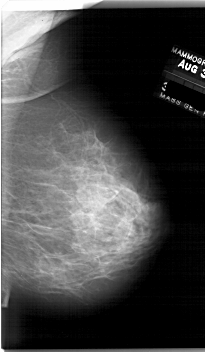

A_1761_1.RIGHT_CC

RIGHT_CC LINES 6256 PIXELS_PER_LINE 3601 BITS_PER_PIXEL 12 RESOLUTION 43.5 NON_OVERLAY